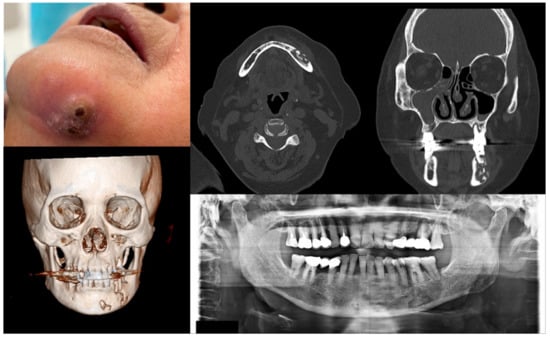

Figure 2.

Case 2 with MRONJ Stage 1: Clinical photo, panoramic view, and computed tomography imaging including three-dimensional reconstruction showing exposed alveolar bone on the anterior maxillary area. An 89-year-old female patient with a history of oral alendronate for more than four years and intravenous administration of denosumab for one year showed the exposed bone after extracting the left upper central incisor three months ago. She reported no symptoms such as pain other than exposed bones. There was no sign of infection, including pus discharge on the exposed bone.